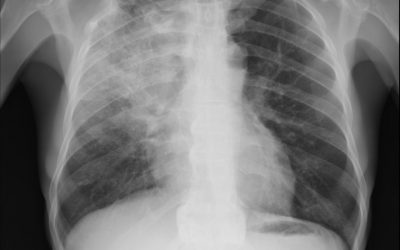

Hydrocortisone in Severe Community-Acquired Pneumonia

Methodology: 4/5 Usefulness: 4/5 Dequin PF, et al. N Engl J Med. 2023 Mar 21. doi: 10.1056/NEJMoa2215145. Question and Methods: Pneumosepsis can lead to pulmonary and systemic inflammation that can increase risk of organ failure and death. The authors attempted to...